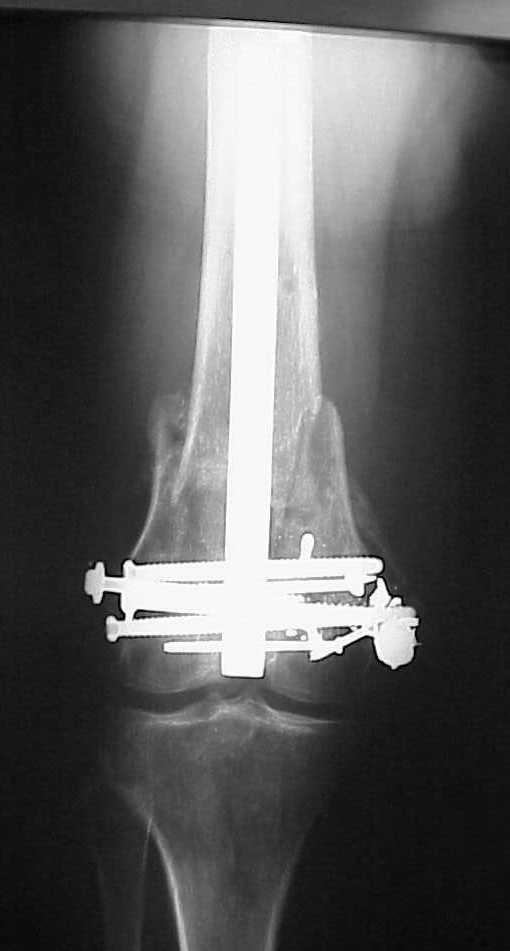

See attached case that was done several years ago before LISS. He had comminuted trochlea and anterior blocking screws were used to prevent anterior IMN cut-out.

Да, примерно так и сделали. Надо было, пожалуй, кончик гвоздя еще спилить, чтобы отверстие было еще дистальнее. Англоязычные коллеги еще

советовали винты в передне-заднем направлении вводить, но что-то не увидел, где там подходящее место.

Since it was done closed the shaft will heal or at worst need an exchange IMN.

Nice job.

Мы пошли на операцию с планом попытаться сделать закрытый интрамедулярный, а не получится - сделать аппаратом. Посчитали, что получилось, хотя на еженедельной конференции ожидаются некоторые проблемы с объяснениями ;-)

Насчет стабильности для ранней нагрузки, конечно, сомнительно, но при таком повреждении ранняя нагрузка противопоказана в любом случае. Для ранних движений Должно хватить. Снимки в следующем сообщении.